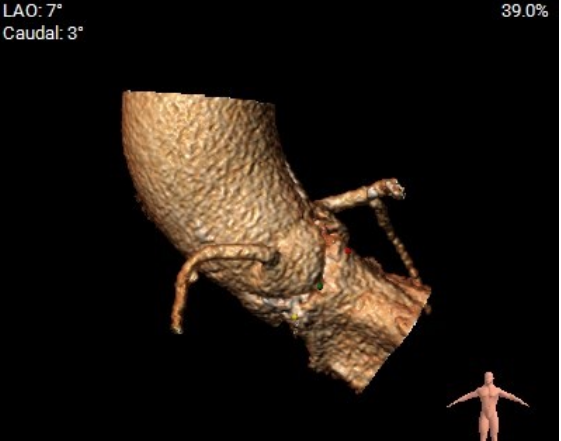

血管三维重建